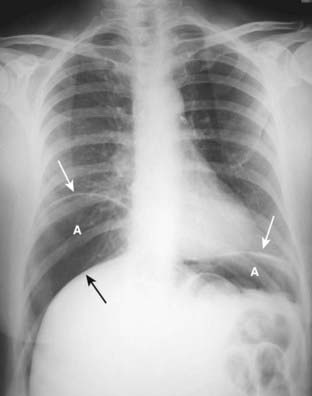

Figure 15-2 Large amount of free air.

Upright view of the chest demonstrates a large amount of free air (A) beneath each hemidiaphragm (solid white arrows). The top of the liver (solid black arrow) is made visible by the air above it. The patient had a perforated gastric ulcer.